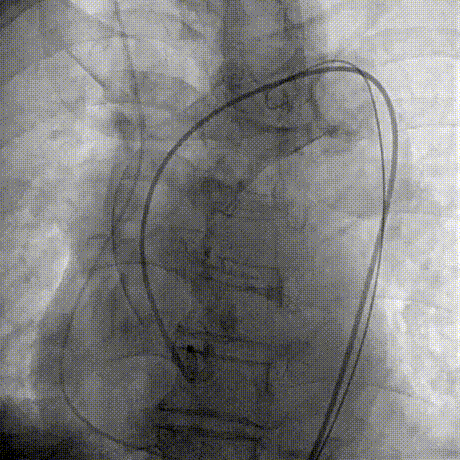

Step 2.建立大鞘通路:大鞘通过升主、边进入边加弯,避免剐蹭弓部斑块

Step 4.输送系统进入:过弓性能优异,悬空通过,整体过程未将鞘管顶起至弓顶部

过弓示意图

手术中其实有个关键点,在可调弯鞘过弓的时候,我们特意放慢了速度,一遍进一遍调弯,确保每一步都不触碰弓顶钙化。这台手术的成功,本质上是 “病变特点和器械特性” 的精准匹配。对同类型来说,碰到瓷化升主动脉合并复杂弓的病例,建议术前一定要把钙化范围、弓部角度这些解剖细节分析透,器械选择上不用局限于单一方案,多考虑协同作用,或许能找到更安全的路径。毕竟对我们来说,每台复杂手术的目标都一样:在保证安全的前提下,给患者带来最好的长期获益。